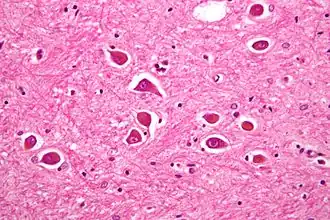

![]() Микрофотография астроцитов Альцгеймера II типа, возникающих при печёночной коме | |